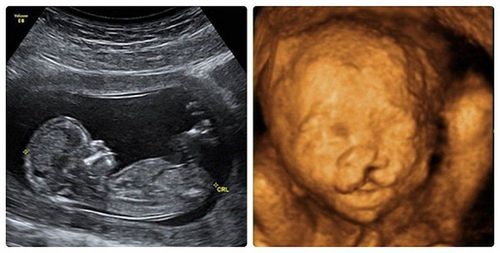

Thai nhi sứt môi có nguy hiểm không?

Em siêu âm thai bị sứt môi, bác sĩ đề nghị xét nghiệm máu, nước ối, gai nhau. Vậy bác sĩ cho em hỏi thai nhi sứt môi có nguy hiểm không? Các xét nghiệm trên có tác dụng gì

Thai nhi 23 tuần sứt môi hở hàm ếch nên làm gì?

Em siêu âm thai 23 tuần, bị khe hở môi, hở hàm. Bác sĩ cho em hỏi thai nhi 23 tuần sứt môi hở hàm ếch nên làm gì? Cảm ơn bác sĩ tư vấn.

Thai nhi 27 tuần bị sứt môi có sao không?

Em bầu được 27 tuần, đi siêu âm được chẩn đoán là bé bị sứt môi. Vậy bác sĩ cho em hỏi thai nhi 27 tuần bị sứt môi có sao không? Em nên làm sàng lọc gì để phát hiện dị tật hay các bệnh cho thai nhi không? Em cảm ơn.